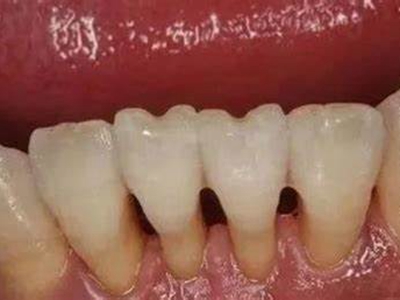

牙龈退缩下排牙龈暴露淡黄色牙根图

牙龈退缩使下排多颗牙齿的牙根暴露在外,牙根比牙冠纤细很多,色泽淡黄,牙齿间的缝隙较大。通常伴有龋齿、根面缺损、牙齿敏感等情况。